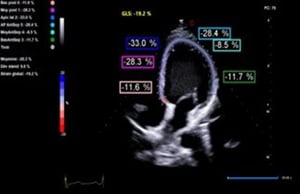

El strain longitudinal global (GLS) mide el acortamiento de las fibras miocárdicas en el eje longitudinal, desde el ápex hacia la base. Este parámetro refleja principalmente la función de las fibras subendocárdicas, que son las más susceptibles al daño precoz.

El GLS permite identificar deterioro funcional en etapas tempranas, incluso cuando la FEVI aún se conserva dentro de valores normales.

El análisis conjunto de la fracción de eyección y el strain miocárdico permite una caracterización más completa de la función ventricular. Lejos de reemplazar a la FEVI, el strain la complementa, aportando sensibilidad diagnóstica en fases tempranas de la enfermedad.